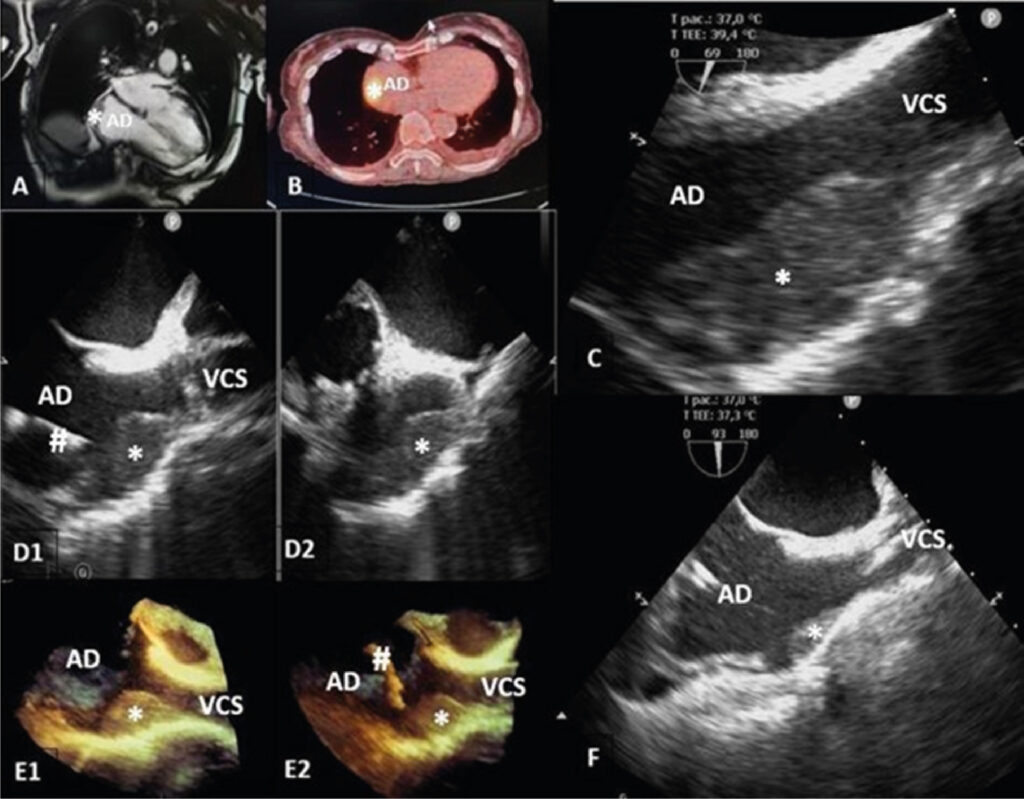

Primary Cardiac Lymphoma: Role of Imaging Multimodality in Diagnosis

Intracardiac masses are a diagnostic challenge since their symptoms can be common to cardiovascular pathologies. Some methods, whether invasive or not, enable differential diagnosis, histological confirmation, and adequate treatment. To better understand the importance of imaging multimodality and the approach to managing cardiac tumors, we investigated a case of a primary cardiac lymphoma in which the multidisciplinary approach allowed rapid diagnosis and treatment, including of intercurrences, with a promising initial response despite fatal progression due to severe acute respiratory syndrome coronavirus 2 infection.